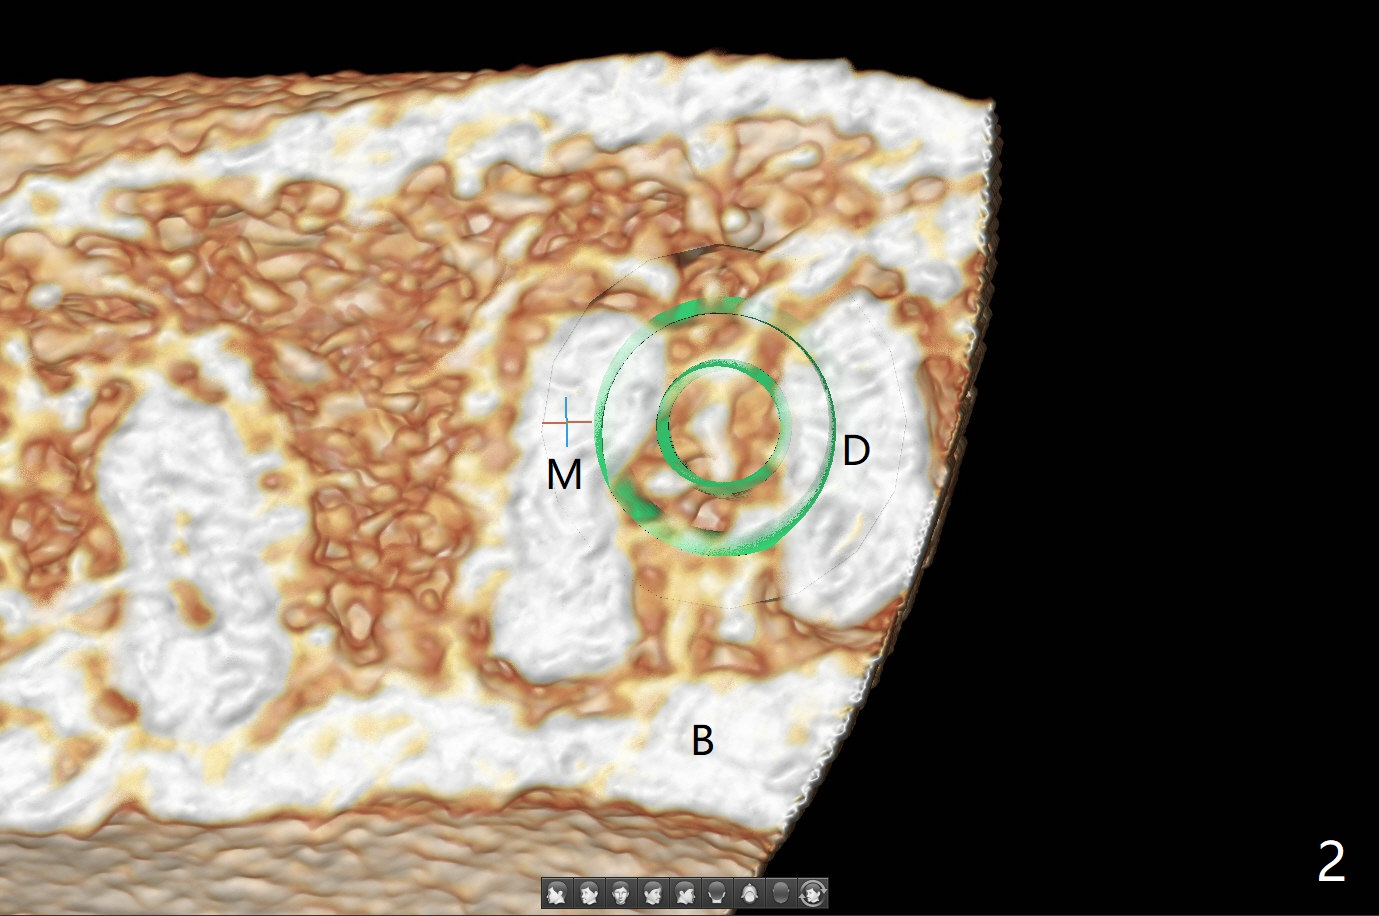

即刻种植即刻修复偶尔出现骨粉丧失,今天我们尝试临时基台,它可以制作像螺丝固位牙冠,可能会减少骨粉流失。左下7颊侧肿胀(图一:*),为了让植体(图二:绿色)植入中隔正中,钻洞时保留近中(M),远中(D)牙根。但是意想不到的是在导板指引下,钻头还是偏移近中(图三),而且颊侧(图四:圆圈),不过颊侧骨板没有缺损。由于牙根存在(硬),钻洞吃力,之后拔除,完成最后一个钻头,放置植体(图五),方位仿佛不错,临时基台(5.2x8(2)毫米)也完全就位,树脂围绕基台制作临时牙冠(图六),最后使用螺丝固位(*),颊侧肿胀牙龈必须用缝线固定(<),减少骨粉损失。由于牙冠与基台连接不好,病人汇报有些骨粉丢失。术后一个月检查尚可愈合正常,病人满意,已经做好思想准备做右下第二磨牙种植。临时牙冠进行修整。术后即刻近中牙槽窝间隙由粘性骨粉充填(图五),四个月后间隙消失(硬骨板也消失,图七),5.2x5(3)毫米粘固基台似乎没有完全就位,可能因为远中牙槽嵴阻挡(图七:*)。小一号基台仿佛完全就位(图八(咬翼片);图七(根尖片,可能失真)),但是临床上没有听到清脆声音(可能软硬组织阻挡)。随着时间推移,远中牙槽嵴吸收,当松动基台螺丝再次拧紧,可能会真正完全就位,必须拍摄完美咬翼片证实。这种植体芯(body, not threads)特别厚内部结构看不清楚。两周后粘固牙冠,然后取出牙冠和基台,清除残余粘固剂,然后复位,拧紧30Ncm。